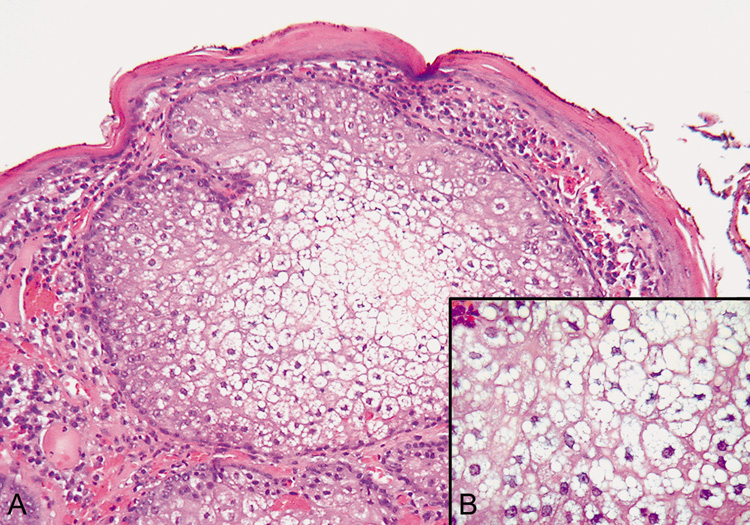

| All of the connective tissue or collagen vascular diseases may affect the